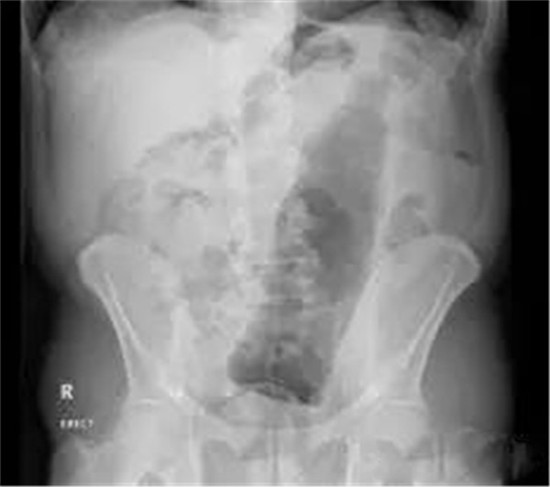

下面我们来看看常见的这些直肠异物。为了保护病人的隐私,X光片已经经过技术处理,看不出任何病人的信息。

这是一个啤酒瓶。男性。

上面是一个啤酒瓶在大肠里。病人是男性。这是常见的肛门内异物。

这种情况,往往只要给病人打上全身麻醉,肛门松弛后,就可以用卵圆钳经过肛门把啤酒瓶拉出来。